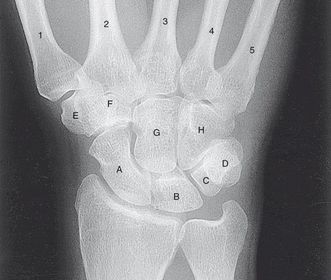

PA and AP Wrist

How many bones make up the hand and wrist?